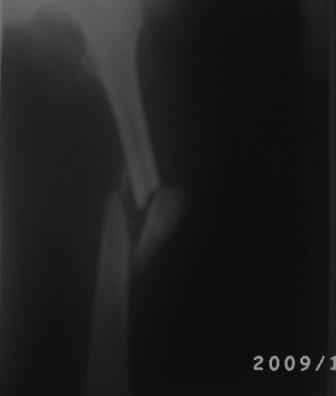

Добрый вечер, уважаемые коллеги. Произведена операция БИОС. Больной 35л, 3-месяца назад получил тяжелую сочетанную травму, после улучшение состояния доставлен к нам, Р-грамма прилагается.

Учитывая поворот большого костного осколка на 180гр. , произведена открытая репозиция, скелетирована только передне-наружная поверхность., антеградный и/м остеосинтез, и наш старенький ЭОП перестал работать, пришлось дистальную блокировку произвести в рентген кабинете под сериоскоп-Сименс, с большими трудностями.

И в конце выяснилось что имеется диастаз задне-внутренной стенки. Заново блокировать рентгенологи не разрешили.